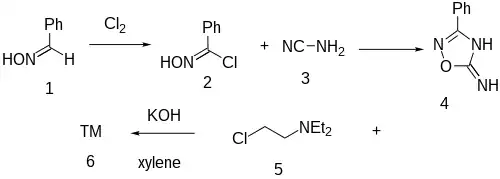

Synthesis

Butalamine has very similar synthesis but is alkylated on the alternate nitrogen position.

The reaction of benzoylchloride oxime [698-16-8] (2) with Cyanamide (3) gives 3-Phenyl-1,2,4-oxadiazol-5-amine [3663-37-4] (4). Alkylation with 2-chlorotriethylamine [100-35-6] (5) in the presence of KOH base occurs at the endocyclic ring nitrogen completing the synthesis of imolamine (6).